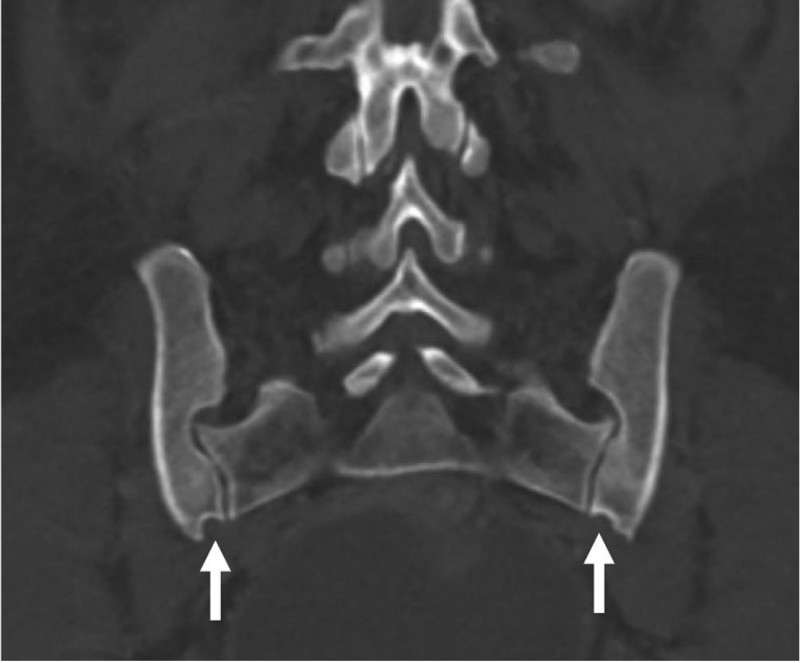

A recent paper in the American Journal of Biological Anthropology, co-authored by KLI group leader Barbara Fischer, challenges the long-held belief that certain pelvic bone features—often called "scars of childbirth"—can reveal a woman's history of pregnancy and birth. Researchers used CT scans to examine the pelvises of women with and without children, as well as men, and found that these bony traits were just as common in women who had never given birth as in those who had. The preauricular sulcus, a groove on the pelvic bone, was found in about half of all women but not in men, suggesting it is linked to sex rather than childbirth. Other features showed no clear connection to pregnancy or delivery. While urinary incontinence was more frequent among women who had given birth, it did not strongly correlate with pelvic bone changes. The study concludes that pelvic skeletal features are unreliable as markers of reproductive history, urging caution in their use for anthropological research.